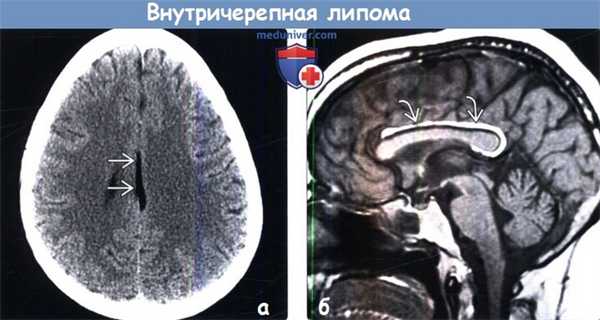

(а) Бесконтрасгная КТ, сагиттальный срез: у молодой женщины, обследуемой по поводу изолированной головной боли, определяется гиподенсная линейная структура, располагающаяся по средней линии.

(б) MPT, Т1 -ВИ, сагиттальный срез: у этой же пациентки выявляется, что линейная структура кри -волинейная межполушарная липома, которая закручивается вокруг заднего отдела гипогенезированного мозолистого тела и направляется в заднюю часть промежуточного паруса. Колено и валик мозолистого тела не полностью сформированы.